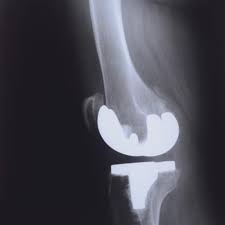

The company ORTHOPEDIC NIKIFOROV was founded in 1998 by the candidate of medical sciences. doctor of orthopedic-traumatologist of the highest category Nikiforov IA Owing to high professionalism and results of work, ORTONIC has gained well-deserved reputation and reputation among colleagues and population of Dnepropetrovsk region and CIS countries (Russia, Moldova, Armenia, etc.). The principle of the enterprise is NO IMPOSSIBLE, it is based on knowledge, experience and active implementation of modern technologies in orthopedics and traumatology. Conservative methods of treatment include individual selection of medicines, therapeutic blockades, manual therapy, massage, physiotherapy (vibration table, magnetotherapy, bioptron, electromyostimulation, etc.), rehabilitation with the suggestion of the necessary concomitant devices and means for the fastest recovery (corsets, bandages, various joint fixators, crutches, walking sticks, etc.). Various minor invasive interventions (chymonucleolysis, vertebroplasty, kyphoplasty, percutaneous nucleoplasty using cold plasma) that are performed on an outpatient basis are successfully used to treat problems associated with spine pathology. The latest modern treatment methods introduced in our company are endoscopic operations using the TYSSES technique of Joimax (Germany) with intervertebral hernias, stenosis and other pathologies of the spine, which allow to avoid complications occurring during open operations and the accompanying general anesthesia. We have many years of successful experience in traditional and modern minimally invasive endoprosthetics of large and small joints, which remains the main direction of our activity. Our company is the exclusive representative of the German company IO International Orthopaedics Holding GmbH, which based on the already known prostheses, its ideas and technological capabilities, has developed and implemented a new concept in hip replacement - an artificial joint prosthesis (ICON). We assist interested colleagues in training the operative technique for installing an artificial joint prosthesis - ICON, both in the workplace and in Germany. For 20 years we have been successfully cooperating with Sanitatshaus Gerd Klinz ortho team, an enterprise that for 20 years has been one of the leading places in Germany for the production of functional prostheses of the upper and lower limbs, as well as cosmetic prostheses of limbs and other body parts (nose, ears, eyeballs, fingers). We have an atmosphere of friendliness and human participation. Politeness, benevolence, the desire to understand and help is the basis of our attitude towards patients. We are always glad to see you and will do our best to make you feel great! We are waiting for you at: Ukraine, Dnepr, Gagarin Ave., 13 (under reconstruction) on all questions to address: tel .: +38 (050) 488-88-92 E-mail: orthonik.ukr@gmail.com Germany, Spine Nano Klinik, Zeppelinstr. 21, Potsdam Tel. +4901801121919 E-mail: kmw.nikiforov@hotmail.de